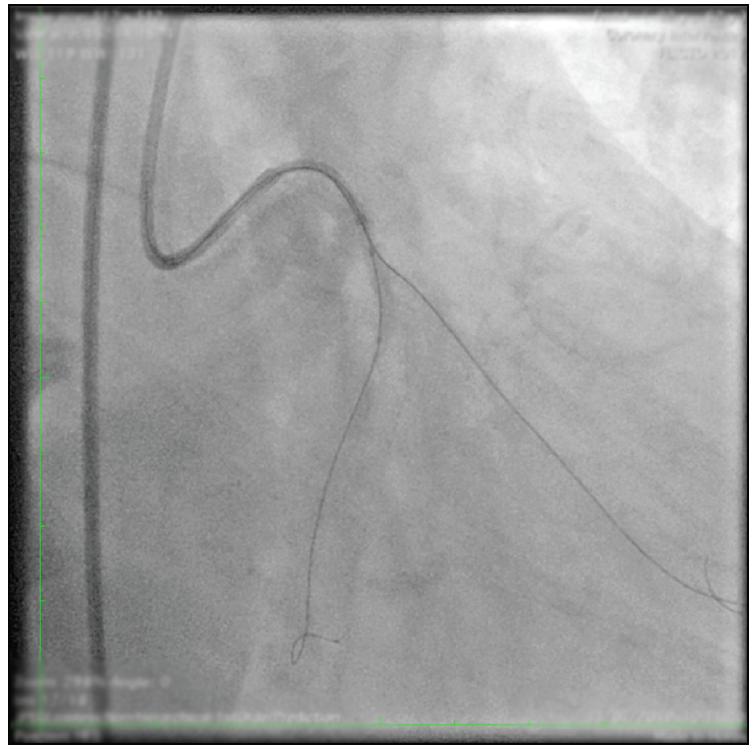

Two months later, the patient underwent percutaneous coronary intervention (PCI) in a staged procedure targeting the LCX. After receiving a 600-mg loading dose of clopidogrel orally and intravenous heparin and nitrates, access was achieved through the right femoral artery with angiographic guidance using a 7-F XB 3.5 Vista Brite Tip catheter (Cordis, a Cardinal Health company) to visualize the target lesion. A Runthrough NS Floppy guidewire (Terumo Interventional Systems) was used to progress and position a FineCross MG microcatheter (Terumo Interventional Systems) at the proximal tip of the LCX lesion (Figure 2). Two Fielder XT-R guidewires (Asahi Intecc USA, Inc.) were passed to the LCX and OM1, respectively. However, after crossing to the distal LCX, the microcatheter did not advance to the OM1 branch.